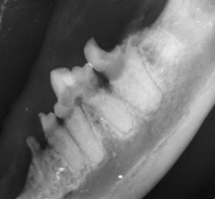

Wichtig: Da FORL oft unter dem Zahnfleischrand beginnt, ist eine Diagnose nur durch ein dentales Röntgen sicher möglich.

2. Dentales Röntgen: Vorab wird die Wurzelstruktur genauestens beurteilt.